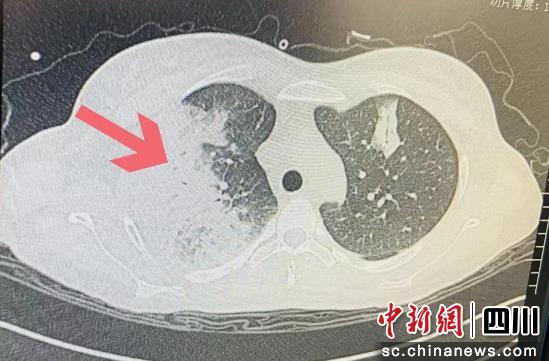

入院后,小梅已出現(xiàn)嚴(yán)重低氧血癥,胸部CT顯示雙肺大面積"白肺"伴胸腔積液,情況已經(jīng)十分危急。